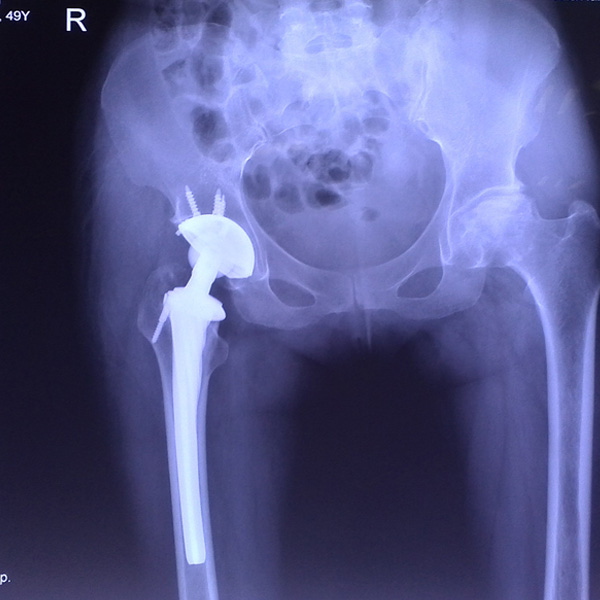

手術(shù)后手術(shù)前

右側(cè)全髖關(guān)節(jié)置換

患者姜某某,女50歲,診斷為“股骨頭壞死”,右側(cè)髖關(guān)節(jié)疼痛到不能生活自理。經(jīng)平臺推薦到哈爾濱醫(yī)科大學(xué)附屬第二醫(yī)院骨關(guān)節(jié)科就診,患者想......